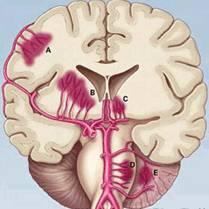

脑出血的严重程度决定于三个方面:出血量-出血部位-病情进展